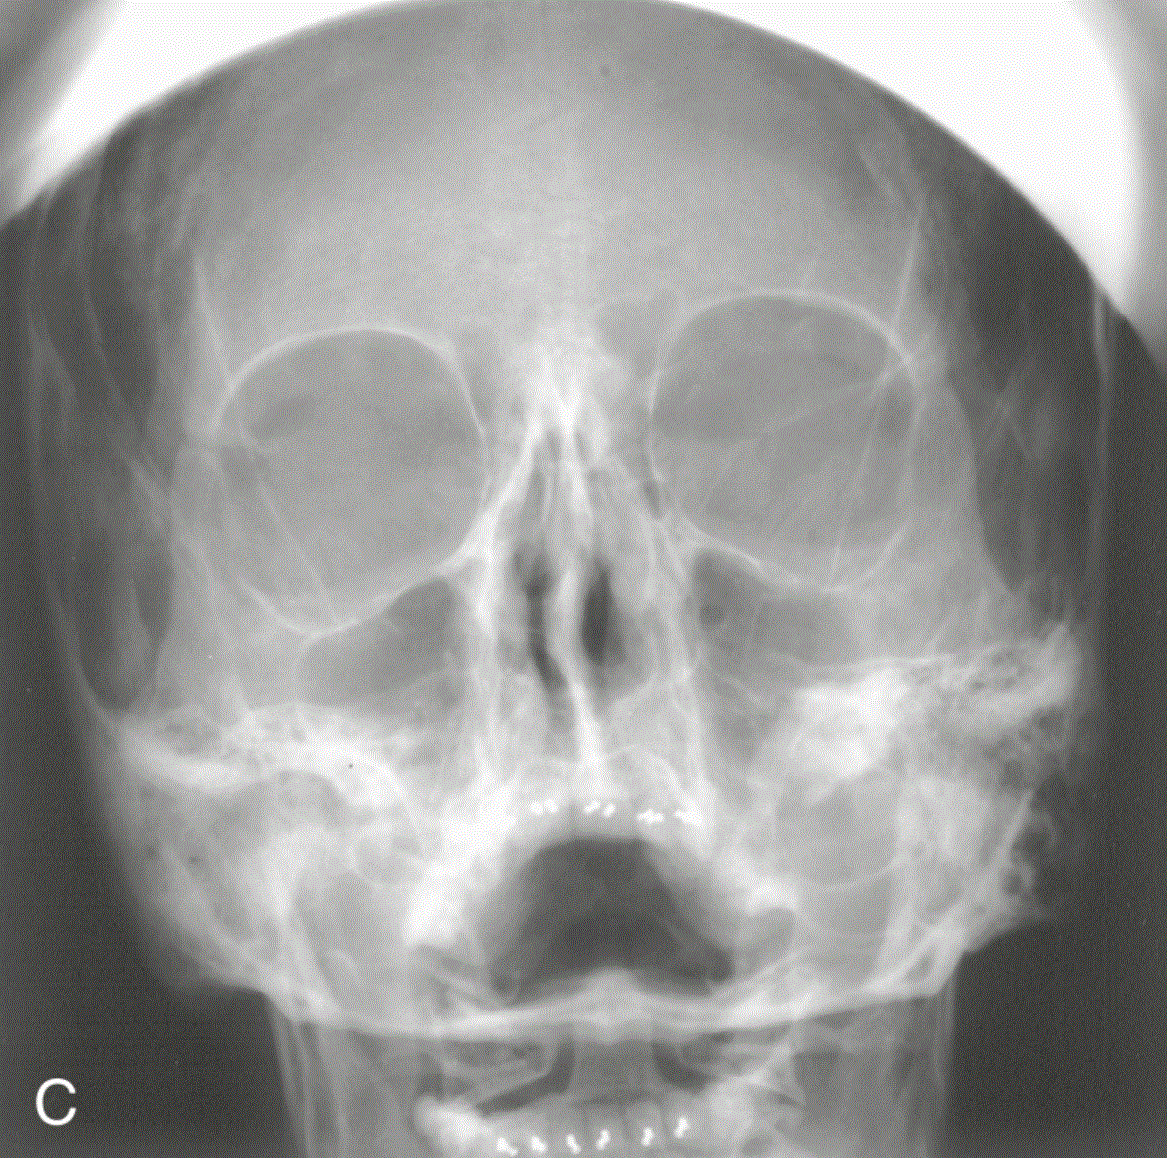

In this image, Water's projection, what action could the technologist take to correct the positioning error?

raise the chin so the OML forms a 37 degree angle with the IR

Which of the following facial bone projections best demonstrates the inferior border of the orbits without superimposition from other structures?

parietoacanthial